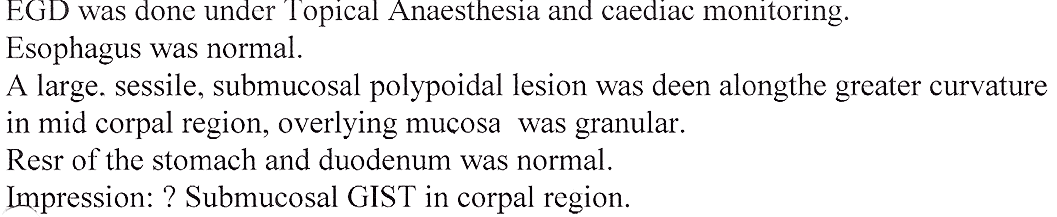

Polyps of the Stomach